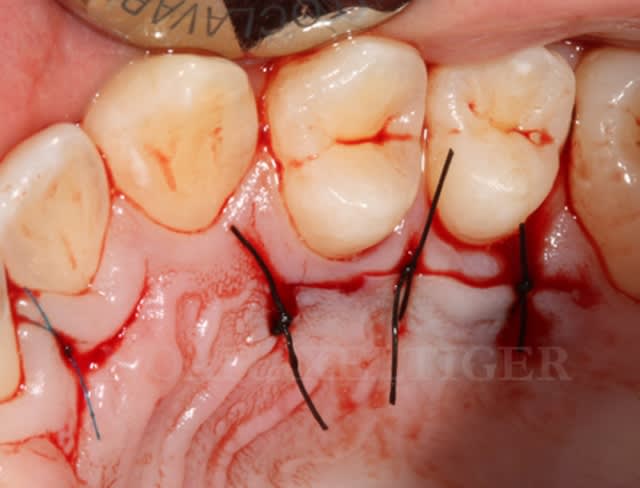

Lit receveur loll9i - Eugenol

Mise en place du greffon conjonctif ejn6xx - Eugenol

Sutures e7ixmz - Eugenol